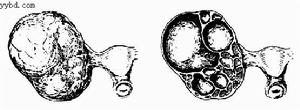

心臟粘液瘤腫瘤大小不一,多有蒂與心房或心室壁相連,外形多樣,外觀富有光澤,呈半透明膠凍狀。切面呈實質性,間有斑片狀出血區及充滿凝血塊的小囊腔。顯微鏡下可見腫瘤細胞呈星芒狀、梭形、圓形或不規則形,散在或呈閉索狀分布於大量粘液樣基質中,胞核多為單核也可呈多核瘤巨細胞。粘液肉瘤瘤細胞形態不一,胞核大,染色深,可見核分裂,瘤細胞可浸潤至小血管內形成瘤栓。

心臟粘液瘤國內外隨著病例數增加,資料積累以及檢查研究手段進展,對心臟粘液瘤的認識已逐漸深化,不能簡單地認為只是一種良性腫瘤。綜合文獻,可將心臟粘液瘤分為兩大類。

1.單純的或散發的心臟粘液瘤 這類粘液瘤占病例的絕大多數,多為單發,並多在典型部位(左心房內房間隔卵圓窩對應部位)生長,或多發(約占病例20%~40%)。患者身體無其他部位的粘液性病變,可於一次常規擇期手術切除後不再發生,心臟及身體各部可完全恢復正常或基本正常。

2.複雜的心臟粘液瘤 包含3個方面:粘液瘤綜合征、家族性粘液瘤、多中心發生的心臟粘液瘤。在這3方面又多有交叉重疊,患者多較年青,心內粘液瘤多不在典型部位生長,臨床表現多較複雜,病勢常較兇猛。